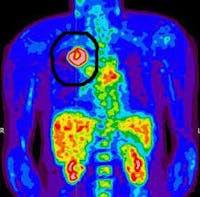

Another misconception of the Warburg Effect is that cancer cells can only use glucose. This is not true. There are two main molecules that can be catabolized by mammalian cell – glucose, but also the protein glutamine. Glucose metabolism is deranged in cancer, but so is glutamine metabolism. Glutamine is the most common amino acid in the blood and many cancers seem to be ‘addicted’ to glutamine for survival and profileration. The effect is most easily seen in the Positron Emission Tomography (PET) scan. PET scans are a form of imaging used heavily in oncology. A tracer is injected into the body. The classic PET scan used fluorine-18 fluorodeoxyglucose (FDG) which is a variant of regular glucose which is tagged with a radioactive tracer so it can be detected by the PET scanner.

Most cells take up glucose at a relatively low basal rate. However, cancer cells drink up the glucose like a camel drinks up water after a desert trek. These tagged glucose cells accumulate in the cancerous tissue and can be seen as active sites of cancer growth.